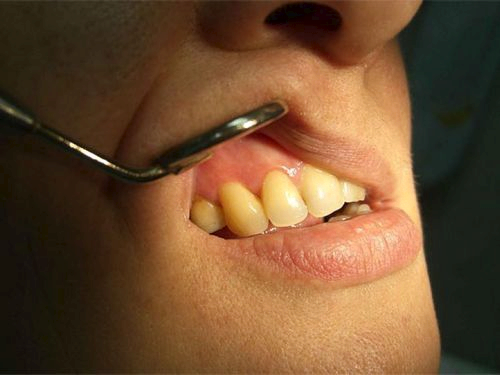

Ось як виглядає кіста на зубі і на знімку: